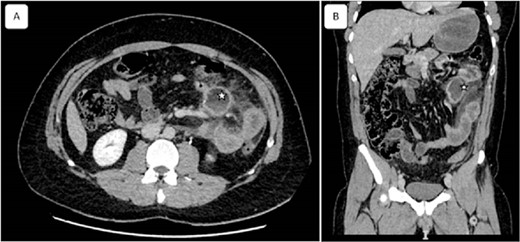

A 32-year-old patient without medical history was admitted to the emergency department for epigastric pain syndrome, which developed 2 days before with worsening symptoms in the last 12 hr. On clinical examination, the patient had no fever and was hemodynamically stable. The abdomen was distended, with widespread pain at palpation. On blood tests, there were stable hemoglobin at 15.9 g/100 ml, a mild inflammatory syndrome with elevated white blood cells at 13.900/mm3 and C reactive protein at 33 mg/L. The CT examination showed diffuse wall thickening of the jejunum and proximal ileum with mesenteric fat infiltration, a mesenteric collection of 51 × 33 mm, and a moderate volume of ascites extending into the pelvis (Fig. 1). A laparotomy was performed, revealing diffuse chemical peritonitis with aspiration of 1 L of chylous ascites. A whitish crater-like lesion with lymphatic fluid outlet was found in the jejunal mesentery, ~50 cm distal to Treitz’s ligament. A monobloc resection of the mesenteric lesion with the affected jejunal segment (Fig. 2) and a manual termino-terminal anastomosis were performed. Postoperatively, an empirical antibiotic therapy (amoxicilline—clavulanic acid 3 g/d, and Gentamicin 5 mg/kg/d) was administered for 3 days only, since the intraoperative bacteriological examination was negative. The abdominal drain was removed after two postoperative days. The patient was discharged without complications on the sixth postoperative day.

Coronal and sagittal views of computed tomography showing a mesenteric collection of 51 × 33 with mesenteric fat infiltration (asterisk) related to the peritonitis caused by the ruptured cyst. Reconstructed images: (A) axial and (B) sagittal view.